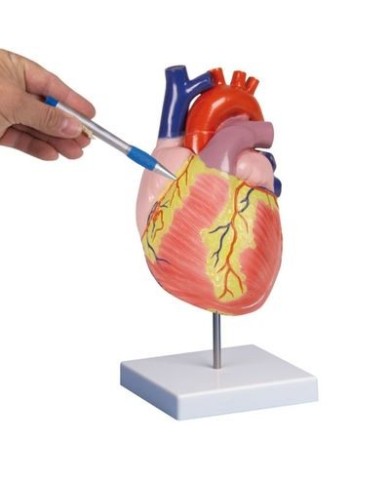

Modello di cuore di alta qualità scomponibile in 5 parti

Modello di cuore di alta qualità scomponibile in 5 parti

Modello anatomico di cuore, ingrandito 2 volte, su cavalletto

Realizzato in stampa 3D ad elevatissima risoluzione a colori.

Realizzato in stampa 3D ad elevatissima risoluzione a colori.

Realizzato in stampa 3D ad elevatissima risoluzione a colori.